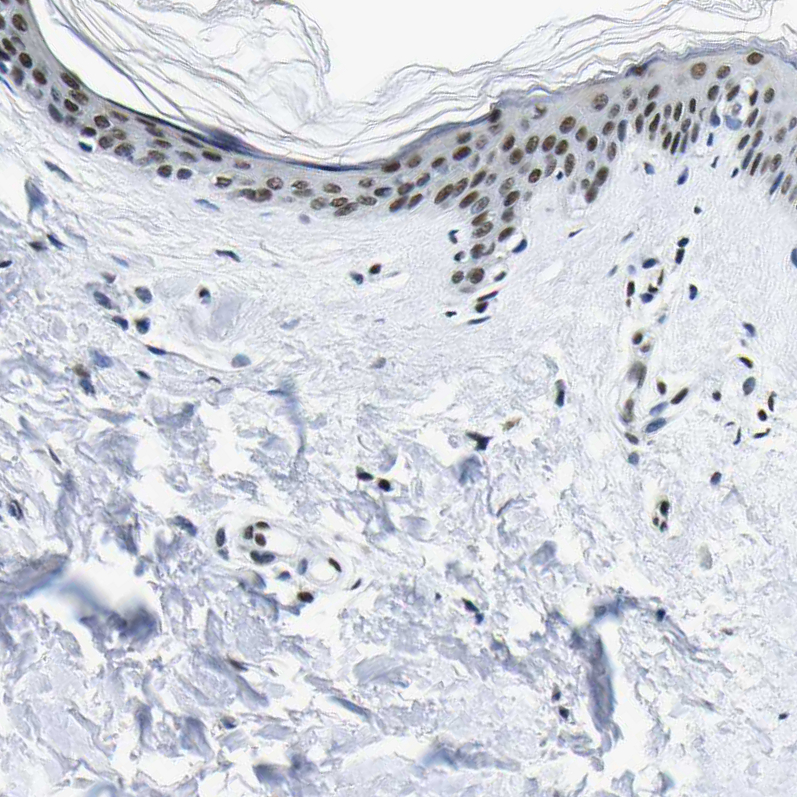

Immunohistochemical staining of human skin shows moderate nuclear positivity in squamous epithelial cells.